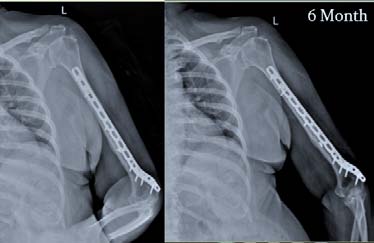

It was a Prospective study conducted at Sri Ramachandra Medical College & Research Institute, Chennai during April 2015 and August 2017. The study consisted patients of closed injury with distal humerus extra-articular fractures in skeletally mature patients, and excluded intra-articular fractures of elbow, paediatric age group, proximal humerus fractures, previouslytreated or operated with other internal fixation methods/devices but failed, open injuries, and patients having a pre-operative neuro-vascular deficit. Preoperatively patients were evaluated clinically, radiologically and the diagnosis was established and classified using the AO/ASIF Classification. Twenty (20) patients of distal humerus extra-articular fractures were at hand of which Nineteen (19) were available for final assessment. Our follow-up period ranges from 6 weeks to 1 year. The Implant used was LCP Extra-articular Distal Humerus Plate, which is anatomically shaped, and angular stable fixation system for extra-articular fractures fixation of the distal humerus. The LCP head is tapered to minimize soft tissue irritation; five distal locking holes accept 3.5 mm locking screws, all head holes are angled medially to maximize screw purchase in bone, two most distal holes are angled toward the capitulum, and trochlea. whereas in the Plate shaft Combi holes combine a dynamic compression unit (DCU) hole with a locking screw hole, providing the flexibility of axial compression, and locking capability throughout the plate shaft, Limited-contact design, Available with 4, 6, 8, 10, 12 or 14 elongated Combi holes to accommodate distal humerus fractures with shaft involvement (figure 1) The patient is nursed in absolute aseptic conditions in the postoperative ward with the limb in hanging position by pillow cover elevation. Parental antibiotics were continued for the first two days followed by oral antibiotics for the next three days. Pain management was done with intra-venous analgesic, and was removed on the 2 nd post-operative day. There after oral analgesics were given. Drain is removed at the end of 48 hrs. As soon as pain subsides, Rehabilitation Protocol is started with physiotherapy. The Active elbow flexion-extension and supination-pronation exercises with the aim of maximum ranges of motion; as soon as possible but as tolerated by the patients. The patient was advised to continue exercises here or any other convenient centre. Sutures were removed during 12 th to 14 th post-operative day. After the surgery, functional evaluation was done with DASH, MAYO and VAS score (figure 3, 4, and 5) at six weeks, three months, six months, and one year.

Road traffic accident was the major cause of injury 63.2%; followed by slip and fall 26.3%, one case of pathological (5.3%), and sports injury (5.3%) each. The mean metaphyseal-diaphyseal angle was 86.21° (SD3.441°, normal 82-84°), the mean humeralulnar angle was 14.63° (SD 2.338°, normal 17.8° valgus), and the mean shaft-condylar angle was 39.84° (SD 1.500°, normal 40°). The anterior humeral line passed through 50.00 % (SD 1.491 %) of the capitellar width (normal, middle third). Flexion movement was good throughout followup, and was statistically significant from 6 weeks to 3 month; 6 week to 6 month, 6 week to 1 year, 3 month to 6 month, 3 month, 1 year respectively, and was not significant at 6 month -1 year. That means patient had almost recovered by 6 week follow-up, little improvement was there up to 1 year from initial time of follow-up. When compared with last 6 month of followup there was no further improvement possible as patient had already achieved there anatomical range of movement (Figure 10). The extension was significantly improved when the patient came for follow-up at 6 weeks, and mean extension was 3.68 ± 6 degrees. Later at 3, 6 months and 1 year where almost normal extension was possible in all cases except complicated cases; thus there was no scope of further extension at latter visits, and test were insignificant statistically (Figure 11). Supination was not statistically significant at any follow-ups. That means the patient had recovered to an anatomical range of movement by 6 week of followup, and there was no further improvement possible (Figure 12). Pronation was not statistically significant at any follow-ups. That means the patient had recovered to the anatomical range of movement by 6 week follow-up, and there was no further improvement possible (Figure 13). Dash score was decreasing over one year. The Score was compared at 6 weeks to 3 month, 6 month, and 1 year respectively; at 3 month to 6 month, 1 year respectively, and at 6 month to 1 year. All intervals were statistically significant (p<0.05) indicating improvement in patients daily activities to normal over 1 year (Figure 14). Mayo score was increasing over a period of one year. The score was compared; At 6 weeks to 3 month, 6 month, 1 year respectively; 3 month to 1 year;, and at 6 month to 1 year. All interval were statistically significant (p <0.05) except at 3 month -6 month period where it was statistically insignificant due to one case of malunion, and implant failure. Otherwise, all patients recovered to almost normal over 1 year (Figure 15). VAS score was minimal at 6 weeks, and was decreasing at later follow-ups. It was found to be significant at 6 weeks i.e. patient were relived of pain by 6 weeks to 3 months. Later it was marginally significant at 6 months but it was due to case of implant failure that came up with aggrieved pain complaints. Otherwise; in other patient's it was insignificant after 3 months as patients were relived of pain, and there was no scope for any further pain relief (Figure 16).

Malunion (Cubitus varus) was seen as the most frequent complication 15.8% of the study group. Infection (CDC Superficial) and Elbow stiffness were seen in 10.5% which was second most frequent complication noticed. Delayed union and implant failure was seen in 1 case (5.3%) each. One infected patient, after getting completely treated for infection, had implant pulled out at 6 months review also she had associated varus deformity , and elbow stiffness. The patient was not willing for deformity correction. She was managed with bursa excision, wound debridement and implant exit followed by antibiotics and regular dressing. One patient had delayed union and associated elbow stiffness; post 6 months fracture healed well. No intervention was done as the patient was unwilling. Only calcium, multi-vitamin supplementation, and supervised exercises were given. One patient with varus malunion had a postoperative superficial infection which was managed with regular dressing and antibiotics. Another varus malunion had no associated complication. Both malunion did not require any intervention as it did not deteriorate any function, and patients were satisfied without come.